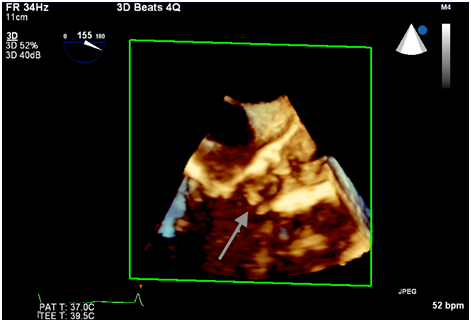

There was a debate whether the echo density represented acute valve thrombosis vs an avulsed native valve leaflet. We believed the former to be less likely given the patient’s pre treatment with DAPT and objective evidence of adequate intraprocedural anticoagulation. However, the patient was transferred to the intensive care unit for continuous monitoring. Anticoagulation with warfarin was initiated. Her hospital course was uneventful and she was discharged to home after 5 days. There was no change in the size of the echo density or severity of aortic regurgitation on pre-discharge TEE. The decision was made to treat the patient with 3 months of anticoagulation with DAPT and warfarin. Follow up TEE at 3 months revealed a persistent mobile echo density, unchanged in appearance from the intraprocedural TEE, confirmed by 3D echo cardio graphic reconstruction (Figure 3). The patient continued to be symptom free and was advised to remain on daily aspirin and warfarin. Clopidogrel was discontinued.

Figure 3 3D reconstructed image 3 months post op showing the persistent mobile mass.

“Silent” acute avulsion of an aortic valve leaflet without annulus rupture might represent a rare complication of TAVR. Our review of the current literature did not unearth any published case series or observational studies, so we are unable to quantify its incidence. The differential diagnosis of an acute mobile echo density during TAVR includes valve thrombosis versus the remnant of native valve tissue. Thrombosis of both the Core valve and the Edward Sapien transcatheter valve, although rare, have been documente.5 Acute valve thrombosis can be fatal and it is extremely important to rule out this diagnosis. Although we were not convinced that the echo density represented thrombus, our team decided to treat the patient with anticoagulation as a precautionary measure due to the potential catastrophic implications. Follow up TEE confirmed our initial diagnosis.

In our case, the echogenicity was believed to be secondary to the native leaflet avulsion since its characteristics remained unchanged on serial echocardiograms. The most likely reason for the prolapse of the native leaflet might have been the tight fit of the delivery system although this cannot be confirmed. A similar entity has been recently reported by Zimmet et al.6 However, aortic annulus rupture was also present and the partially avulsed leaflet resulted in hemodynamic instability requiring further treatment.4 In our case, the patient remained stable and was asymptomatic.